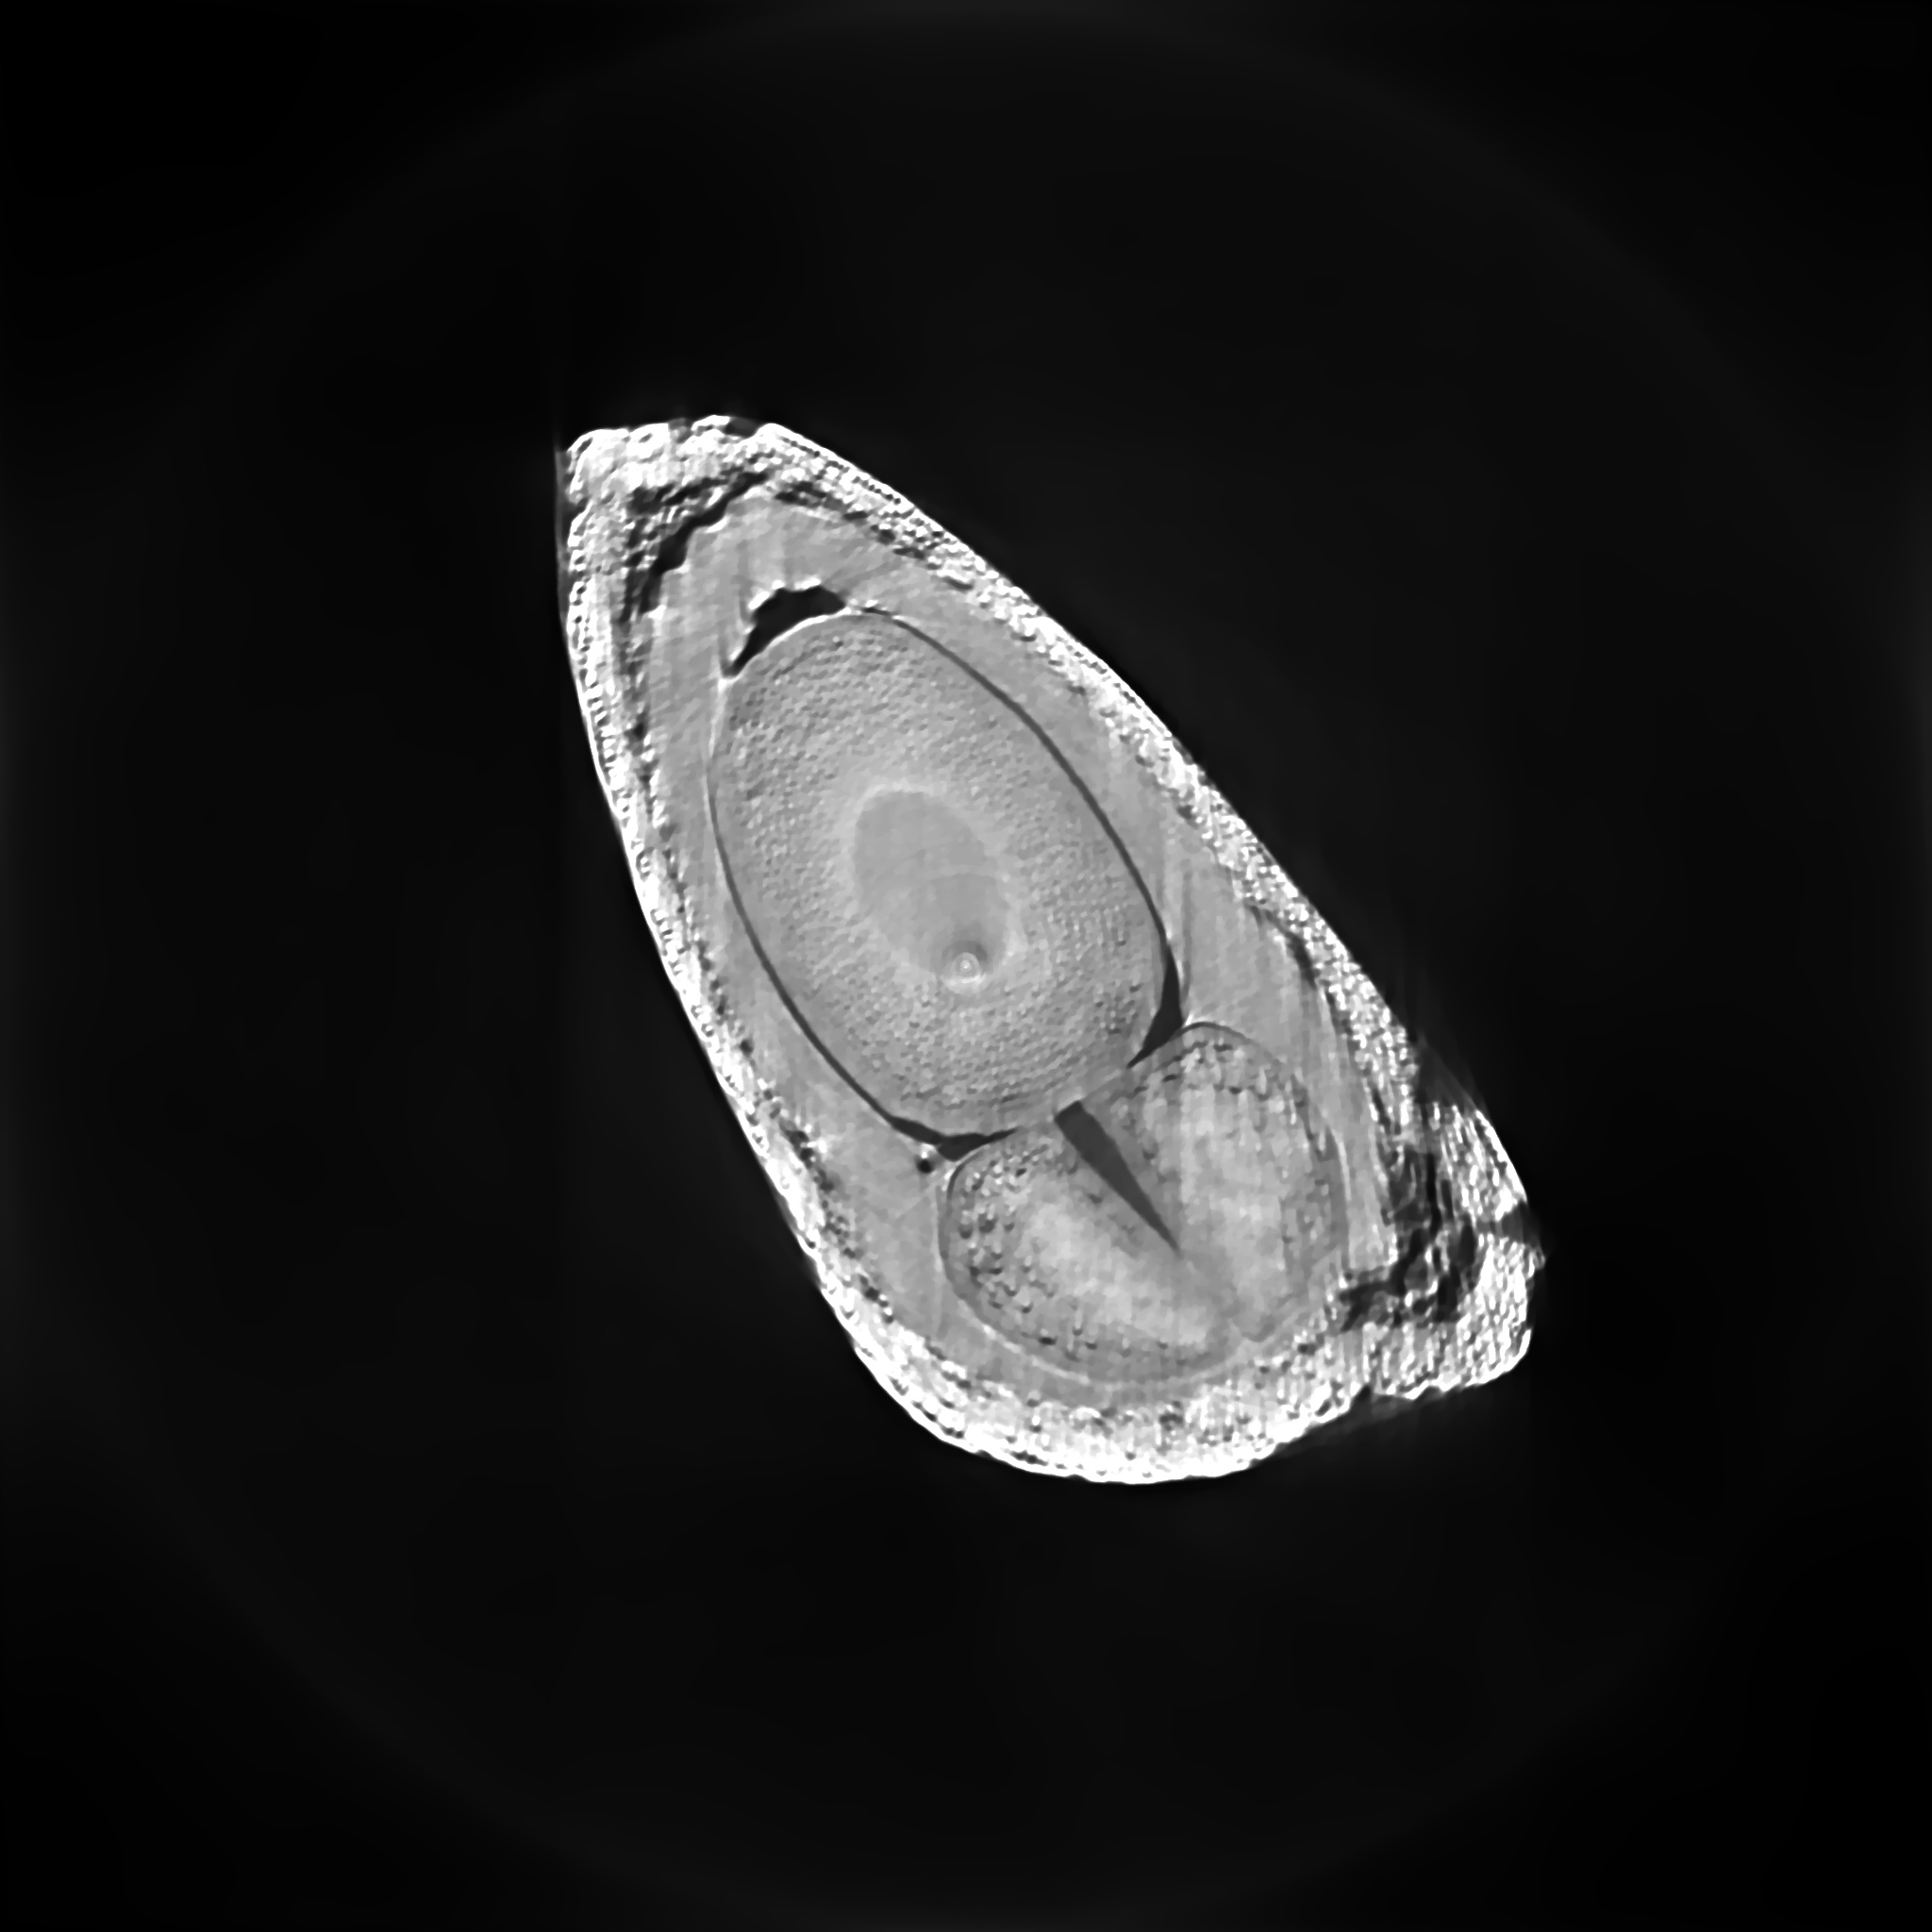

Data for this set of experiments was obtained at the Imaging Beamline (imx) of the Brazilian National Synchrotron Light Source (lnls) through illumination of an apple seed by x-rays. Each radiographic image was pixels in size and the sample was rotated by between each of the images, thereby totaling, for each slice to be reconstructed, views times rays of tomographic count data . Reconstructed images have dimensions of pixels.

The left side of Figure 5 shows the objective function value as a function of computation time for ssaem- and ssaem-tv- with . Notice that increasing the number of subsets speeds up convergence in terms of reduction of objective function value over time. Superiorization reduces this convergence speed, but the fastest methods without superiorization give rise to the fastest superiorized methods as a rule of thumb.

The graphic on the right of Figure 5 displays plots of the objective function value versus total variation for the iterates of each method. The curves make clear that the superiorized version of the algorihtms always present the better compromise between data adhesion and smoothness when compared to its respective non-superiorized version. Figure 6 shows how this property translates to better image quality in practice. The lower row of Figure 6 shows isocontours overlaid on top of details of the images, in order to show that the superiorized image is noticeably smoother, therefore potentially more useful for visualization tasks. If, on the other hand, some apparent detail seems to have been removed from the image, part of these fine details may be reconstruction artifacts but we make no claims in this direction. Notice that these results are in accordance with those obtained using saem and its superiorized versions presented before.

We are grateful to lnls for providing the beamtime for the acquisition of tomographic data for the apple seed reconstruction experiments.